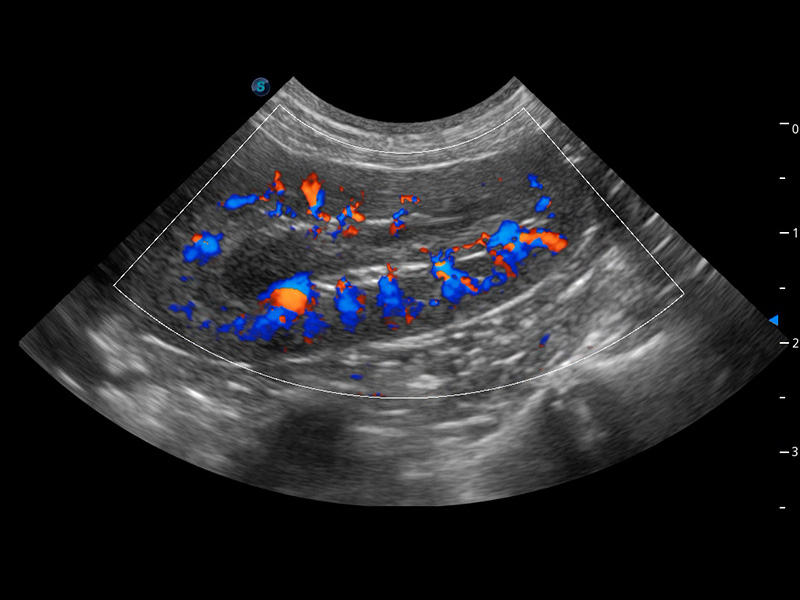

4T血流成像 微察秋毫

融合不同血流成像技术的优势,即可以提升血流成束性,同时可提高血流的视觉敏感性。

PDI 能量多普勒血流

提供高灵敏度和空间分辦率的血流图像,获得更加真实和丰富的诊断信息。

SR Flow 高分辨率血流成像

能够清晰显示细小、低速血流图像,获取传统彩色多普勒技术难以得到的细节和信息。

Micro F 显微血流成像

通过创新的Matrix E自适应滤波器和超长时间域算法,极大提升超低速微细血流的检出能力,同时更精准地滤除软组织和噪声信号,为兽用医生提供以往无法通过常规血流获得的疾病诊断信息。

Bright Flow 立体血流成像

在传统二维血流成像的基础上,呈现血流的立体感,具有动感的生命力之美。精确区分不同血管的空间关系,提高了血流的视觉敏感性。

(犬)肾脏血流